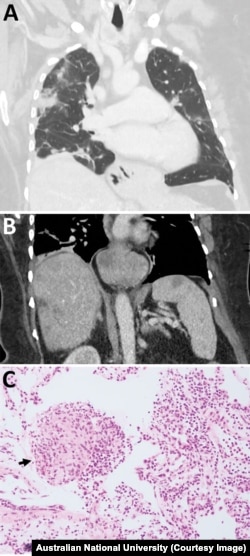

آسٹریلوی مریضہ کے دماغ کا عکس

جنوری 2021 میں انہیں ہسپتال میں داخل کر لیا گیا۔ اور ایک سکین میں ان کے دماغ میں کوئی ابنارمیلٹی دیکھی گئی۔

محققین کی ٹیم کو خدشہ ہے کہ اس کیڑے کا لاروا یا بہت ابتدائی کیڑے اس خاتون کے جسم کے دیگر حصوں مثلاً پھیپھڑوں اورجگر جیسے اعضاء میں موجود ہو سکتے ہیں۔